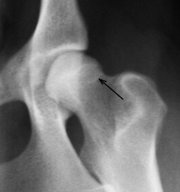

Differentialdiagnosen Diagnostisch muss eine Hüftgelenksdysplasie von anderen Störungen des Skelettsystems abgegrenzt werden. Neben Knochenbrüchen und Luxationen sind dies bei großen Hunderassen vor allem Tumoren der Knochen, welche im Bereich des Femurs relativ häufig auftreten. Bei kleinwüchsigen Tieren muss die aseptische Femurkopfnekrose (Legg-Calvé-Perthes-Krankheit) abgegrenzt werden. Weiterhin treten bei schnellwachsenden Hunden häufig Ablösungen des Gelenkknorpels auf (Osteochondrosis dissecans), die ebenfalls schmerzhaft sind. Ferner sind Erkrankungen des Kniegelenks (z. B. Kreuzbandriss), Beckenbrüche und Erkrankungen der Wirbelsäule (Bandscheibenvorfall, vor allem bei kleinen Hunderassen) sowie Instabilität am Lenden-Kreuzübergang der Wirbelsäule (Cauda-equina-Syndrom, häufiger beim Deutschen Schäferhund) auszuschließen. BehandlungMan kann HD nicht heilen, sondern nur das Auftreten klinischer Symptome und das Fortschreiten der Krankheit hinauszögern oder die Schmerzen reduzieren. Je häufiger der Hund bestimmte Bewegungsabläufe ausführt, desto schneller verschleißt die Hüfte. Zu diesen Bewegungen gehören vor allem jene, die die Gelenke besonders stauchen, wie Treppenlaufen, Springen auf harten Untergründen und ähnliche. Man kann dem Hund mit frühzeitigem Erkennen und richtigem Umgang mit der Krankheit ein normales Leben ermöglichen. Es gibt folgende Behandlungsmöglichkeiten: